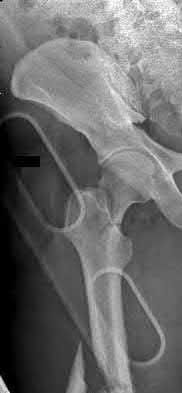

1013) A 60-year-old woman sustains the injury shown in Figure 75. Prior to her injury, she lived independently and was a community ambulator without need for any assistive devices. What treatment will give her the greatest long-term painless hip function with the lowest reoperation rate?

5. Open reduction and internal fixation with an intramedullary device Corrent answer: 1

Cemented hemiarthroplasty is typically used to treat displaced femoral neck fractures in elderly patients. Recently, however, there has been a growing realization that many of these patients would be candidates for total hip arthroplasty had they presented with arthritis rather than fracture. Recent randomized studies have demonstrated improved outcomes up to 4 years following total hip arthroplasty compared with hemiarthroplasty in pain and functional scores. The rate of dislocation is higher following total hip arthroplasty. However, some patients with hemiarthroplasties required later conversion to total hip arthroplasty because of acetabular wear. In situ pinning is not recommended for patients with a displaced fracture. Open reduction and internal fixation of displaced femoral neck fractures in elderly patients is not recommended because of the risk of nonunion and osteonecrosis.